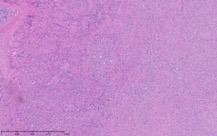

As part of the patient’s treatment, the thoracic surgery team performed a right middle and lower lobectomy. A 4-cm mass in the right bronchus intermedius without invasion into the lung parenchyma was revealed, and pathology confirmed the diagnosis of leiomyosarcoma. The sections of pulmonary tissue from the right middle and lower lobectomy showed a spindle cell tumor most consistent with leiomyosarcoma (Figure 3a-d). Most of the tumor was low grade, with some foci showing high-grade nuclear atypia and increased mitotic activity. Despite these rare mitotic figures, there was no evidence of necrosis. Following surgery, chemotherapy was planned for the patient. However, the patient’s postoperative course was complicated by persistent hypoxic respiratory failure, hypovolemic and hemorrhagic shock, and acute kidney injury. Her respiratory status continued to decline, and she went into cardiac arrest with pulseless electrical activity. She was resuscitated; however, her shock and respiratory failure worsened despite aggressive therapy. Her family chose to transition her to comfort care, and the patient died.

The immunohistochemistry staining also lent additional support to the diagnosis of leiomyosarcoma. As would be expected for such a diagnosis, both vimentin and desmin were immunoreactive. The tissue also stained positive for muscle markers including smooth-muscle actin, muscle-specific actin, and desmin, thus supporting the histological diagnosis of low-grade (highly differentiated) leiomyosarcoma. The tissue stained negative for S100, therefore pointing away from melanoma as a potential diagnosis. The immunohistochemistry profile also included pankeratin staining to distinguish a potential carcinosarcoma with sarcomatoid differentiation, and this test result returned negative.

The patient’s malignancy followed the typical behavior of endobronchial leiomyosarcoma. These tumors are expected to expand locally, although there was no evidence that her tumors had yet reached this stage of invasion. After lobectomy, surgical pathology of the mass obstructing the bronchus intermedius demonstrated that the tumor had not invaded the visceral pleura, nor were there positive margins at the bronchial, vascular, or parenchymal margins. The tumor was 1 cm from the closest margin. Also in alignment with the diagnosis of a low-grade leiomyosarcoma, there was no evidence of malignant spread to any of the 4 lymph nodes histologically examined, and Ki-67 staining highlighted less than 5% of cell nuclei in the right lung mass and less than 1% of cell nuclei in the left lung mass. Her tumor staging was pT3 pN0.